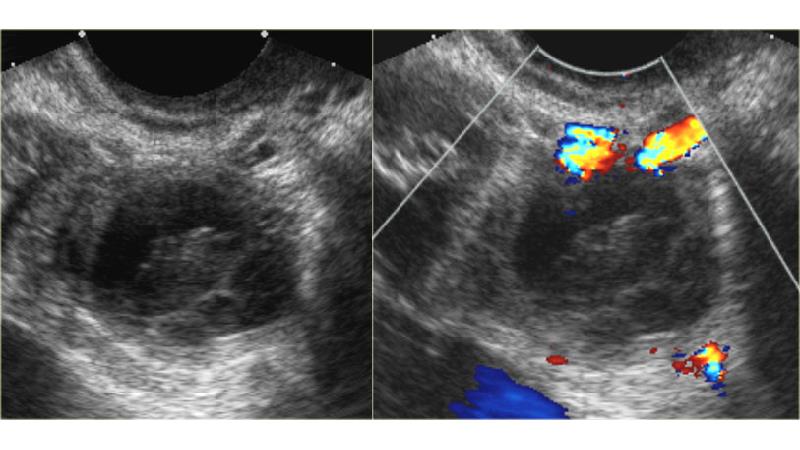

پاره شدن کیست تخمدان هموراژیک

ظواهر غیر معمول تولید شده ناشی از پاره شدن کیست تخمدان هموراژیک سبب تولید خون در درون لگن می گردد.

این موقعیت به طور مایع اکوژنیک اطراف کیست و رحم است، چنانچه خونریزی شدید باشد، امکان دارد هموپریتونیوم خون داخل کیسه موریس مشاهده شود. این صورت پاره شدن مشابه بارداری خارج از رحمی است.